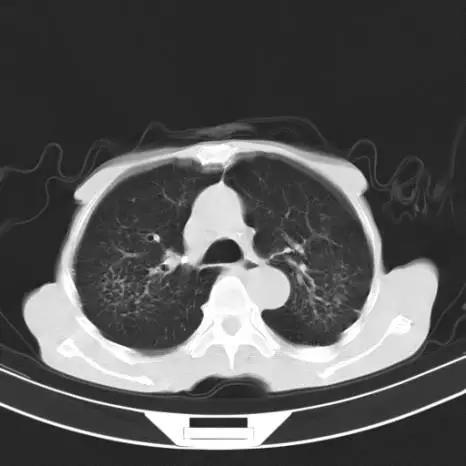

首先,展示一张肺部ct图像,从直观上介绍一下